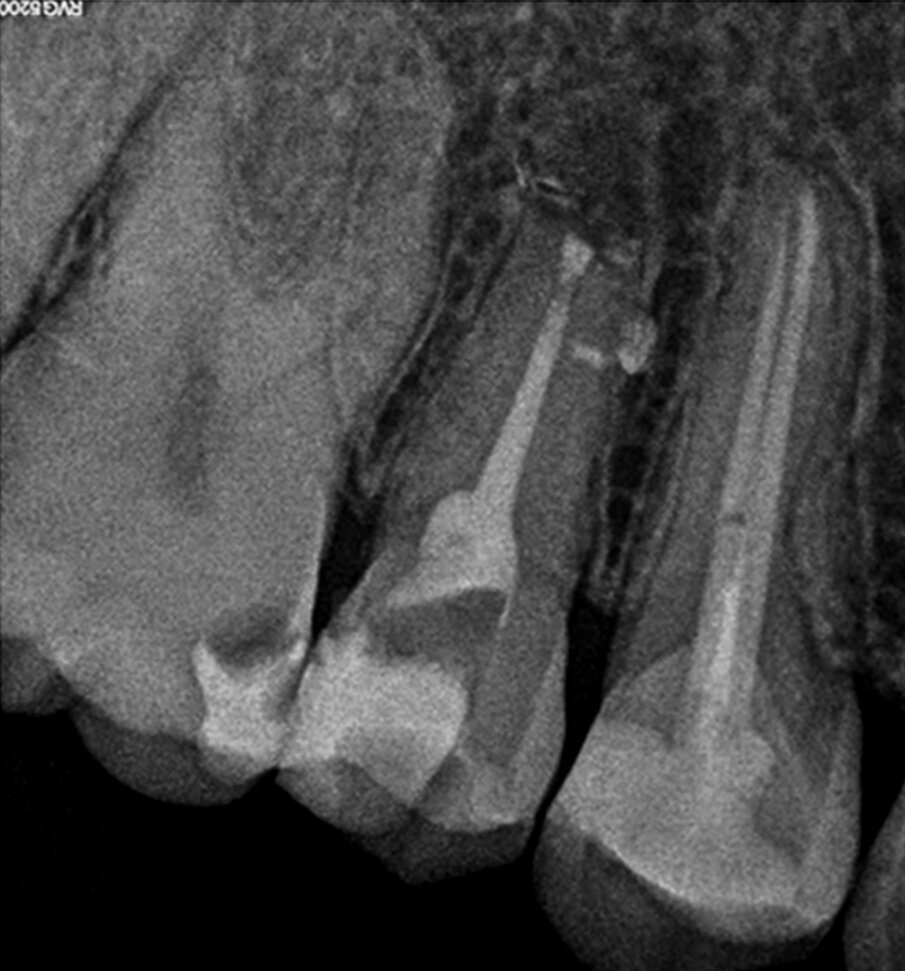

A 38-year-old female patient consulted owing to moderate pain associated with her previously treated maxillary right second premolar. Her medical history was non-contributory. Clinical examination revealed that the tooth was slightly sensitive to vertical percussion. Periodontal probing depth and mobility were within normal limits. A periapical radiograph showed the presence of a separated instrument outside of the root (Fig. 2a), and a preoperative CBCT scan demonstrated that the buccal bone plate was intact (Figs. 2b & c). Endodontic retreatment had been performed five months earlier. The diagnosis for tooth #15 was previously treated symptomatic periapical periodontitis, and the treatment of choice was guided EMS.

Under local anaesthesia, a full-thickness mucoperiosteal‑ap was reflected, providing visualisation of the buccal bone (Fig. 2g), and the printed template was used to mark the cortical window (Fig. 2h), which was cut with a Piezotome CUBE LED handpiece, and the separated instrument was exposed (Fig. 2i) and removed (Fig. 2j). After apicectomy, retro-preparation was done using ultra sonic tips (ACTEON) and sealed with TotalFill BC RRM Fast Set Putty (FKG) (Fig. 2k). The ‑ap was sutured using 5/0 prolene suture material (Fig. 2l). The sutures were removed 72 hours postoperatively. After two years the patient came to our office for a follow-up radiograph, the tooth was asymptomatic and in function (Fig. 2m).

Fig. 2k: Post-op radiograph after apicectomy, retro-preparation and retro-filling with TotalFill BC RRM Fast Set Putty.